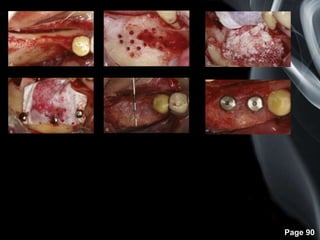

Page 90